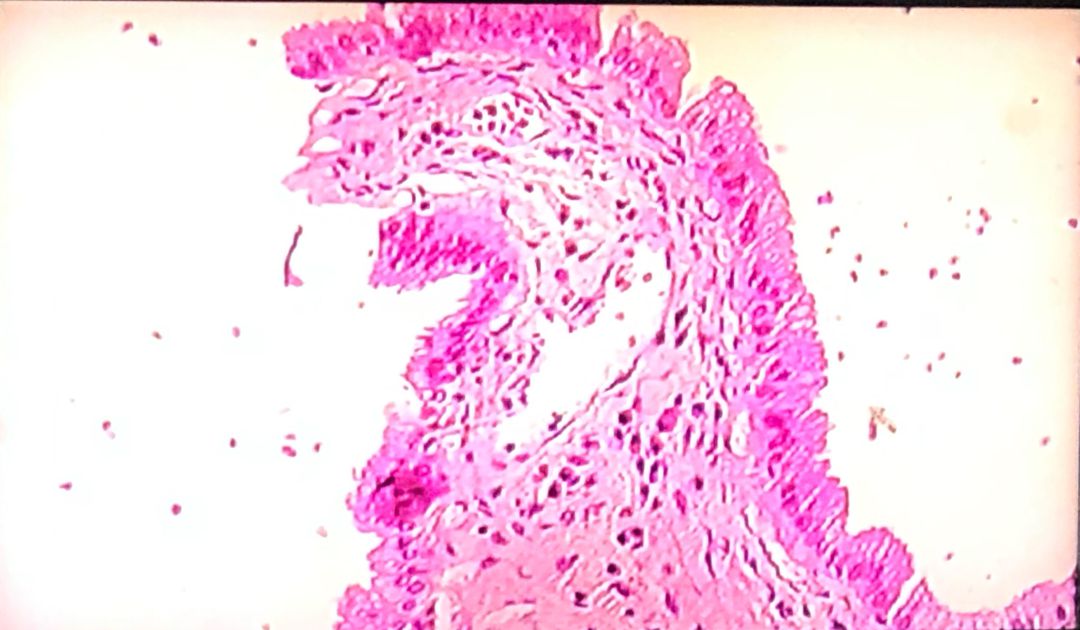

Bladder epithelial tissue

Under microscope

Microscope

Bladder

Epithelial